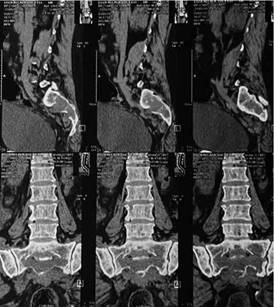

Contamos con los siguientes estudios de gabinete: tomografía de columna lumbar (Figura 1) que reporta discopatías regresivas lumbares asociadas a espondiloartrosis, lesión expansiva osteolítica en el sacro y que estrecha los neuroforamenes S2 - S3 y S3 - S4. Hallazgo por el cual se decide hacer biopsia guiada por TAC, la cual es exitosa, encontrándose tejido friable, se envía muestras a anatomía patológica e inmunohistoquímico el cual reporta plasmocitoma óseo (Figura 2).

Figura 1: Tomografía de columna lumbar que reporta discopatías regresivas lumbares asociadas a espondiloartrosis, lesión expansiva osteolítica en el sacro y que estrecha los neuroforamenes S2 - S3 y S3 - S4